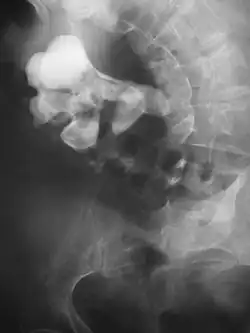

Calcium-containing stones are relatively radiodense (opaque to X-rays), and they can often be detected by a traditional radiography of the abdomen that includes the kidneys, ureters, and bladder (KUB film).[59] KUB radiography, although useful in monitoring size of stone or passage of stone in stone formers, might not be useful in the acute setting due to low sensitivity.[60] Some 60% of all renal stones are radiopaque.[61][62] In general, calcium phosphate stones have the greatest density, followed by calcium oxalate and magnesium ammonium phosphate stones. Cystine calculi are only faintly radiodense, while uric acid stones are usually entirely radiolucent.[63]

Where a CT scan is unavailable, an intravenous pyelogram may be performed to help confirm the diagnosis of urolithiasis. This involves intravenous injection of a contrast agent followed by a KUB film. Uroliths present in the kidneys, ureters, or bladder may be better defined by the use of this contrast agent. Stones can also be detected by a retrograde pyelogram, where a similar contrast agent is injected directly into the distal ostium of the ureter (where the ureter terminates as it enters the bladder).[61]

Bilateral kidney stones can be seen on this KUB radiograph. There are phleboliths in the pelvis, which can be misinterpreted as bladder stones. -